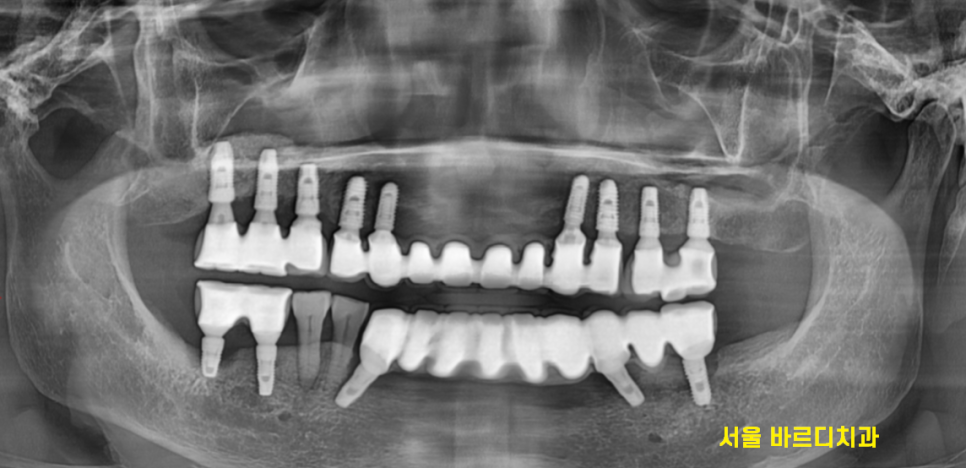

엑스레이 사진에서도 보이지만

치료를 참 많이 하신 환자분입니다.

전악 임플란트를 하셨고

남아있는 내 치아는 딱 2개

오른쪽 아래 작은 어금니만 본인 치아셨습니다.